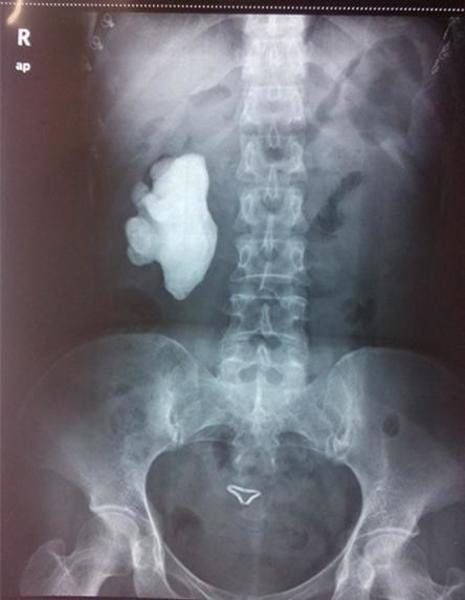

右肾铸型结石术后kub平片(西门子泌尿x线诊疗系统):肾结石无残留ems清